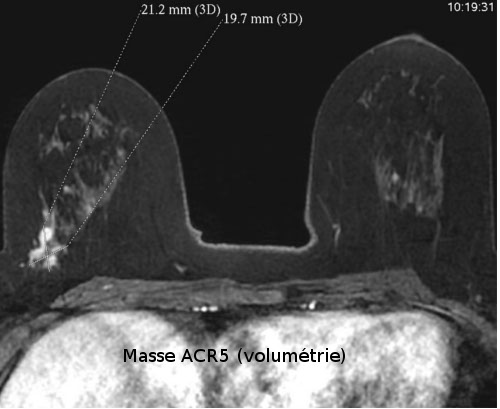

La morphologie de la lésion observée et la visualisation d'une ou plusieurs zones prises de contraste sont les principales informations fournies par l'IRM.

Une image de morphologie irrégulière surtout, et une prise de contraste associée avec courbe de type 5 (prise de contraste précoce, rapide et intense avec phase de lavage secondaire appelée "wash-out") oriente avec une probabilité d'environ 80% vers une lésion maligne (cancer). Selon le contexte médical la morphologie et l’aspect des prises de contraste des lésions peuvent traduire certaines pathologies du sein, notamment de nature cancéreuse.